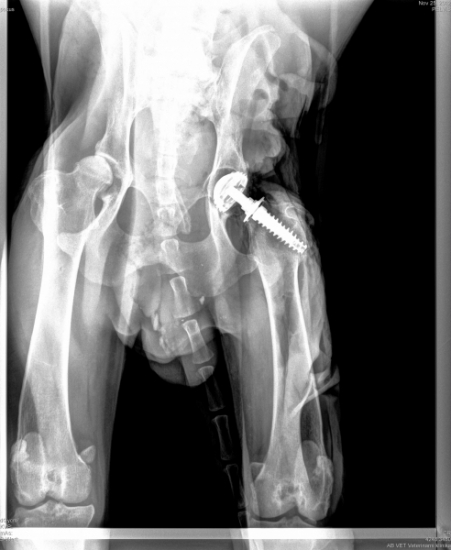

Endoproteza stawu biodrowego.

Kwalifikowane są ciężkie psy, u których występuje zaawansowana dysplazja ze znaczną bolesnością. Tej metody nie stosuje się u młodych zwierząt z nierozwiniętym w pełni układem kostnym. Nie nadaje się też dla psów, u których współistnieją inne schorzenia narządu ruchu (np. problemy natury neurologicznej czy kłopoty z innymi stawami).